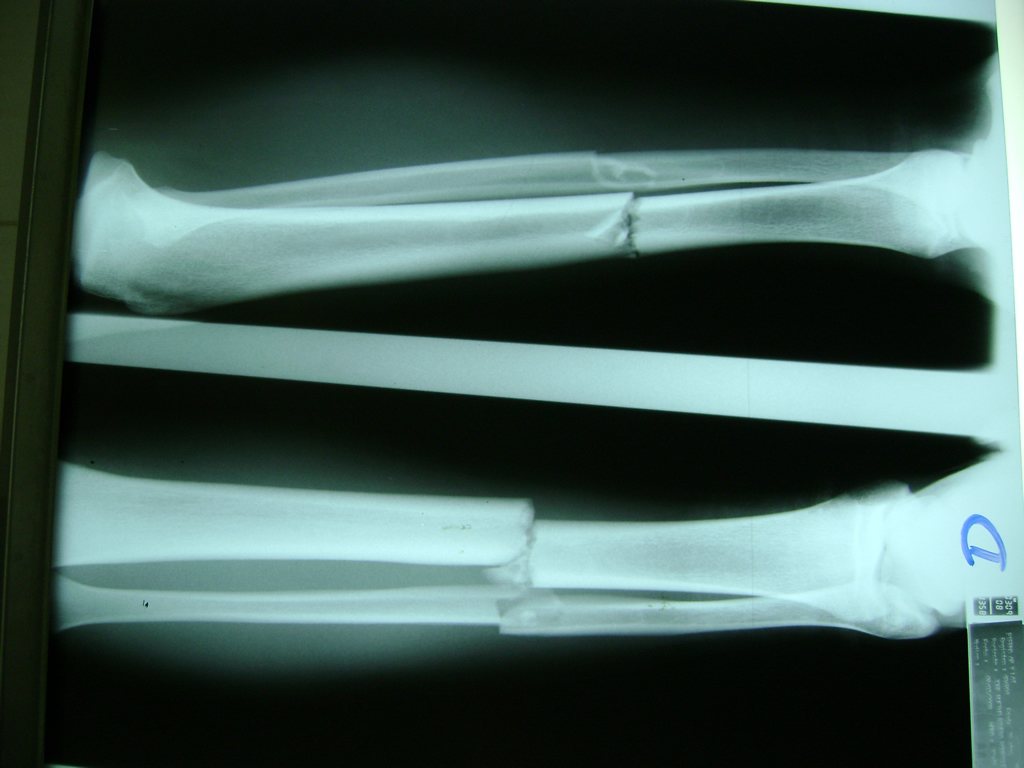

Cirugías de Peroné y Tibia

Aunque cada uno de estos huesos puede fracturarse por separado, normalmente la rotura es una lesión que se produce de forma conjunta

La mayor parte de las roturas implican a la parte proximal del hueso (parte del hueso próximo a la rodilla) o a la parte distal (parte del hueso cerca del tobillo).

Debido a la fina cobertura de piel que recubre la tibia y el peroné, las fracturas generalmente son abiertas, es decir, el hueso roto rasga la piel, atravesándola. Las fracturas de tibia y peroné generalmente se producen por un fuerte impacto o torsión.